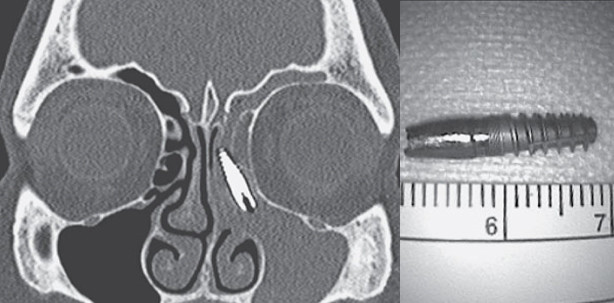

Innerhalb von zwei Jahren nach einer Implantation wanderte die Metallschraube in ihre Nasennebenhöhle und verursachte dort eine äußerst schmerzhafte Entzündung. Die Stelle im Oberkiefer, an der das Implantat eigentlich sitzen sollte, war inzwischen wieder verheilt.

Das Implantat befand sich im Sinus der Frau. Es konnte mittlerweile chirurgisch wieder entfernt werden. © Dr. Alberto Schreiber